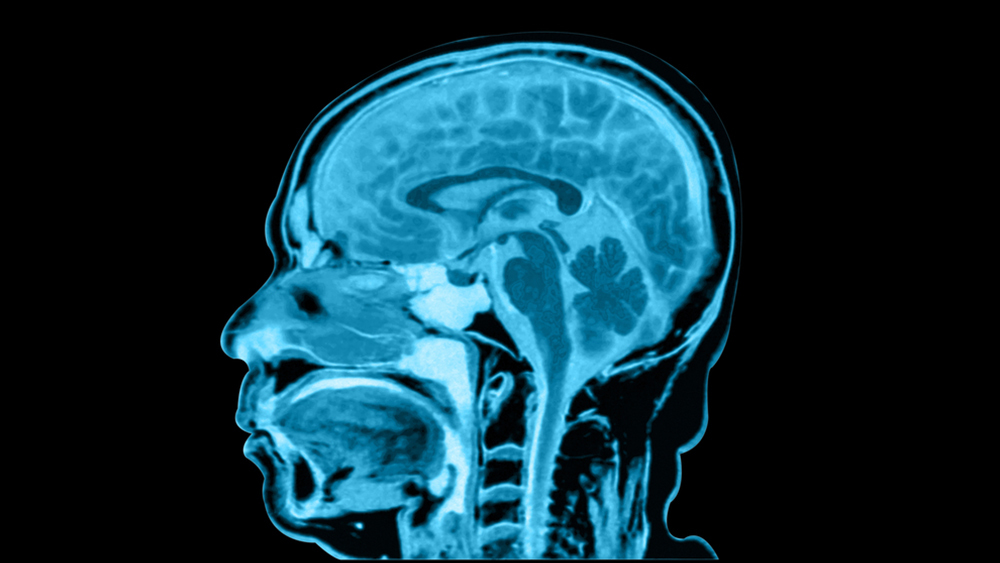

Алекс Уайт, доцент нейробиологии в колледже Барнарда (Нью-Йорк), рассказал в интервью Live Science, что процесс чтения начинается с регистрации форм букв в зрительной коре — области мозга, отвечающей за обработку визуальных данных. Далее информация передается в левую часть веретенообразной извилины — структуру, участвующую в обработке сложных визуальных сигналов. Там находится визуальная область формы слова (Visual Word Form Area -VWFA), которая «узнает» буквы и частые комбинации, называемые биграммами (например, «ст», «но», «ли»).

«После того, как зрительная кора регистрирует буквы, нейроны активизируются при наличии определенных комбинаций букв, а не целых слов», — объясняет Уайт.

Эти биграммы действуют как строительные блоки: мозг распознает знакомые шаблоны и восстанавливает слово целиком. Такой механизм особенно важен на ранних этапах обучения чтению.

Исследования, проведенные с детьми в возрасте до и после начала обучения чтению, и опубликованные в журнале iScience, показали: VWFA формируется и «настраивается» под конкретный язык.

Пример — иврит, где большинство слов пишется без гласных. Тем не менее, читатели легко понимают текст. Это подтверждает, что VWFA может эффективно распознавать шаблоны даже в неполных формах.Удаление гласных создает двусмысленность. Согласные активируют несколько возможных слов, и мозг выбирает то, что лучше всего подходит по смыслу. Это процесс — ментальное автодополнение.